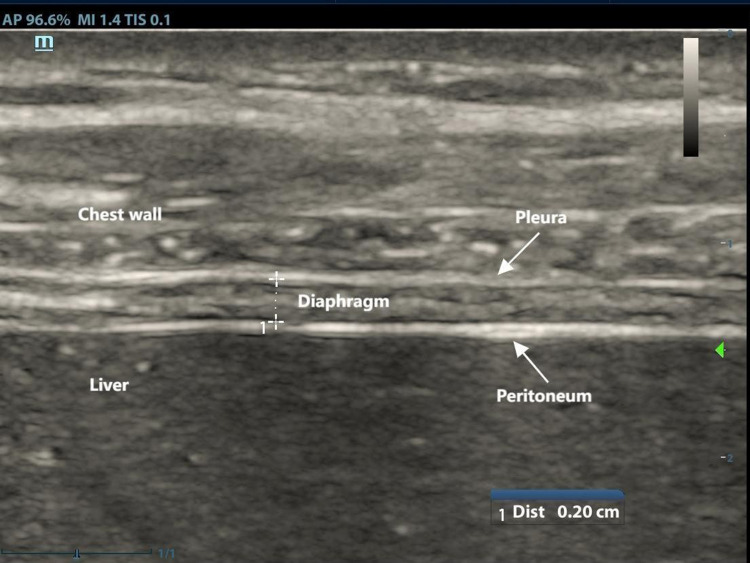

Methods: This study consecutively enrolled 75 COPD patients and 75 healthy subjects. Measurements of diaphragm contraction, motion-related parameters and tissue Doppler imaging (TDI) parameters were conducted and recorded. Clinically relevant data were collected. Baseline demographics, spirometry results, and ultrasound data were compared between COPD patients and healthy subjects. Receiver Operating Characteristic (ROC) curve was constructed to evaluate the diagnostic value of diaphragmatic ultrasound parameters for COPD patients.